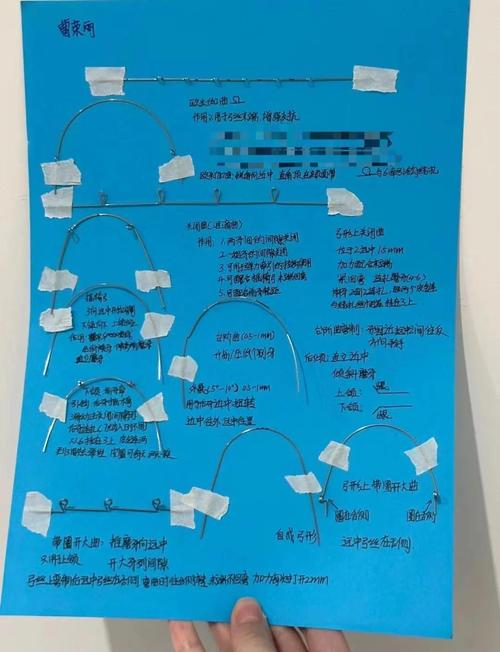

基本弯制技巧与步骤

弓丝弯制需遵循“从简单到复杂、从整体到局部”的原则,以下为临床最常用的基本弯制技巧:

(一)初始弓形弯制

- 选择弓丝:根据牙弓大小选择合适长度的不锈钢丝(比牙弓长度长4-6mm),用弓丝成形器弯制标准弓形:先确定尖牙位置,将弓丝弯制为尖牙宽略大于前牙宽、后牙区逐渐展宽的对称形态,弓丝末端向舌侧回弯(防止刺激颊黏膜)。

- 调整高度:用测量尺标记磨牙托槽位置,将弓丝弯制为与牙弓平面平行的直线,确保所有托槽槽沟在同一平面上(整平阶段的关键)。

(二)基本曲的弯制

- 欧米曲(Omega曲):用于维持牙弓长度,防止前牙内收时后牙前移,用梯形钳在尖牙远中弯制“Ω”形曲,曲的高度为5-7mm,宽度为3-4mm,两侧对称,曲的顶端朝向龈方,避免干扰咬合。

- 停止曲(Stop Loop):用于精确控制弓丝长度,如关闭间隙时限制前牙移动距离,用细丝钳在弓丝两侧弯制“L”形曲,曲的角度为90°,末端回弯2-3mm,防止滑脱。

- 泪滴曲(Tear Drop Loop):用于内收前牙,提供柔和的持续力,用转矩钳在弓丝上弯制泪滴状曲,曲的颈部宽1mm,底部宽3mm,高度4mm,角度为45°,确保力量传递均匀。

(三)转矩与轴倾度控制

转矩是方丝沿长轴旋转产生的力,用于控制牙齿的唇舌向倾斜(如上颌前牙根舌倾、下颌前牙根唇倾),弯制时需用转矩钳,将方丝嵌入钳子垂直槽沟中,旋转钳子至所需角度(如上颌前牙转矩+13°,下颌前牙转矩-7°),旋转范围不超过45°,避免弓丝变形,轴倾度通过在托槽槽沟内调整弓丝角度实现,如磨牙近中倾斜5°,防止近中移动时支抗丧失。